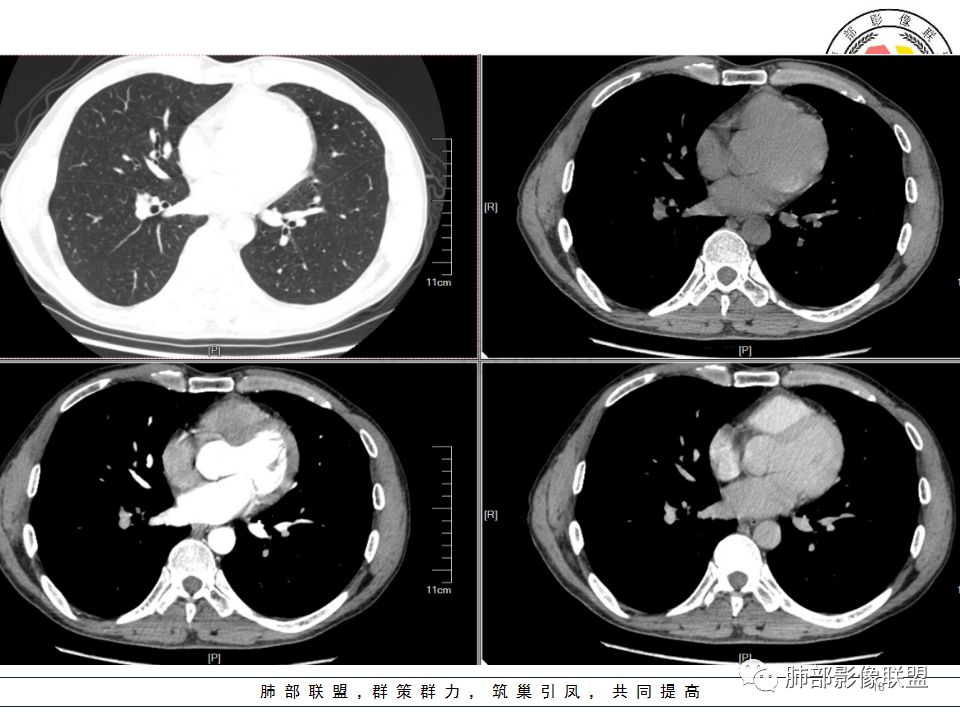

支气管树爬行征这个观点是袁怀平老师提出来的。当时提出了一个观点,就是说支气管是通畅的。

现在就是支气管树爬行征的认定问题,就是关于支气管通与不通?如果堵塞,在哪个区域堵塞?

支气管树爬行征就是肉芽肿性病变,不过它是沿着支气管周围间质往里面走的。我们以前认定支气管要通畅的,但是我们读了隐球菌发现,包括肺炎性肺癌,你就发现外围的病变往内带进展,可以支气管堵塞,例如隐球菌有个特点非常明显的,一个大片状影,支气管在中近端堵塞。我们反推过来,结核也可以这样变化;支气管爬行征原来是要求支气管通畅,改良为支气管可以通畅,也可以在中间堵塞。

该如何判断支气管树爬行征,还需要大宗数据进行观察总结。

支气管树爬行征:肺内结核性肉芽肿的特征性CT征象之一